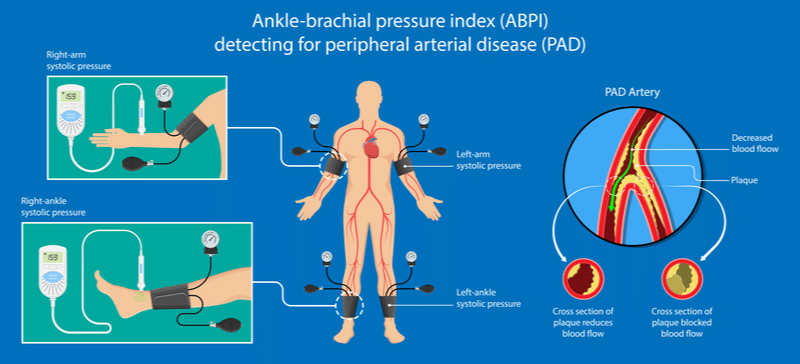

Τι είναι ο σφυρο-βραχιόνιος δείκτης;

Ο σφυρο-βραχιόνιος δείκτης υπολογίζεται μετά από μέτρηση της αρτηριακής πίεσης στα κάτω και τα άνω άκρα. Ο λόγος που προκύπτει από αυτές τις δύο μετρήσεις είναι ένας από τους σημαντικότερους δείκτες υπολογισμού της ισχαιμίας των κάτω άκρων.